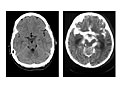

• Imaging tests.

An MRI or CT scan may show bleeding, swelling, or other changes in the brain caused by encephalitis.